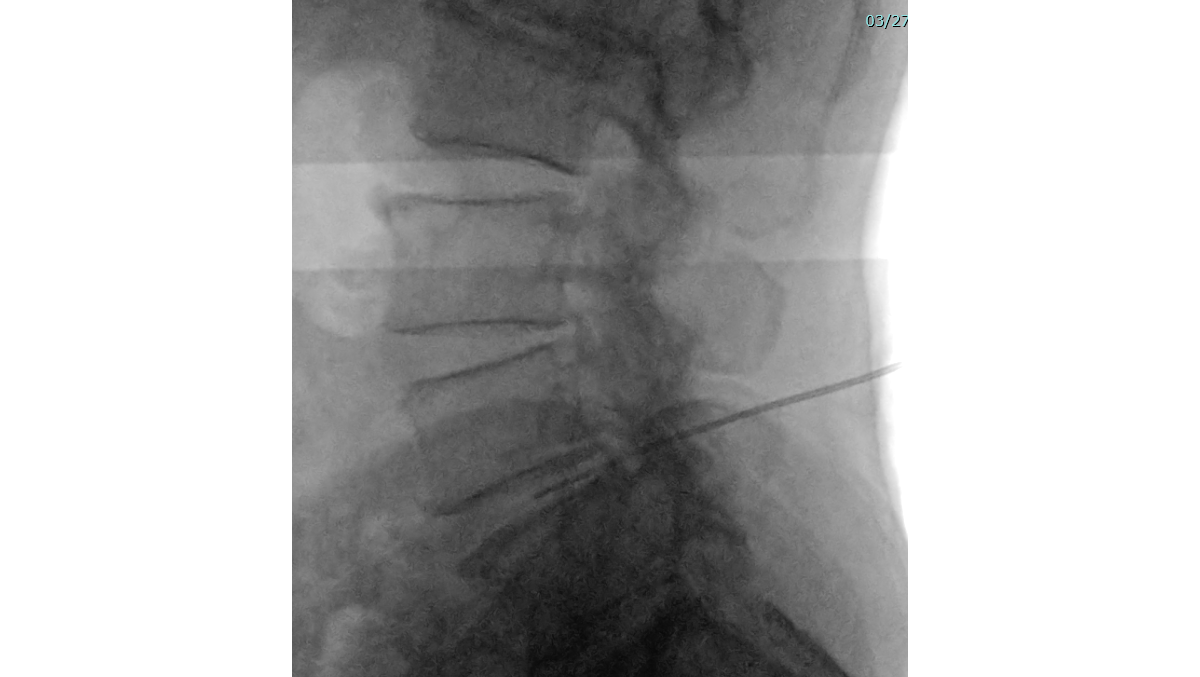

- PLDD(経皮的レーザー椎間板減圧術)

腰痛の根本原因でもある「腰椎椎間板ヘルニア(L4/5)」を取り除くため、症状のあるL4/5の1か所に「PLDD(経皮的レーザー椎間板減圧術)」を行いました。PLDDは、背中からレーザーファイバーが通った針を刺し、飛び出した髄核にレーザーを照射する治療法です。画像は実際、今回の患者さんに施術している様子です。